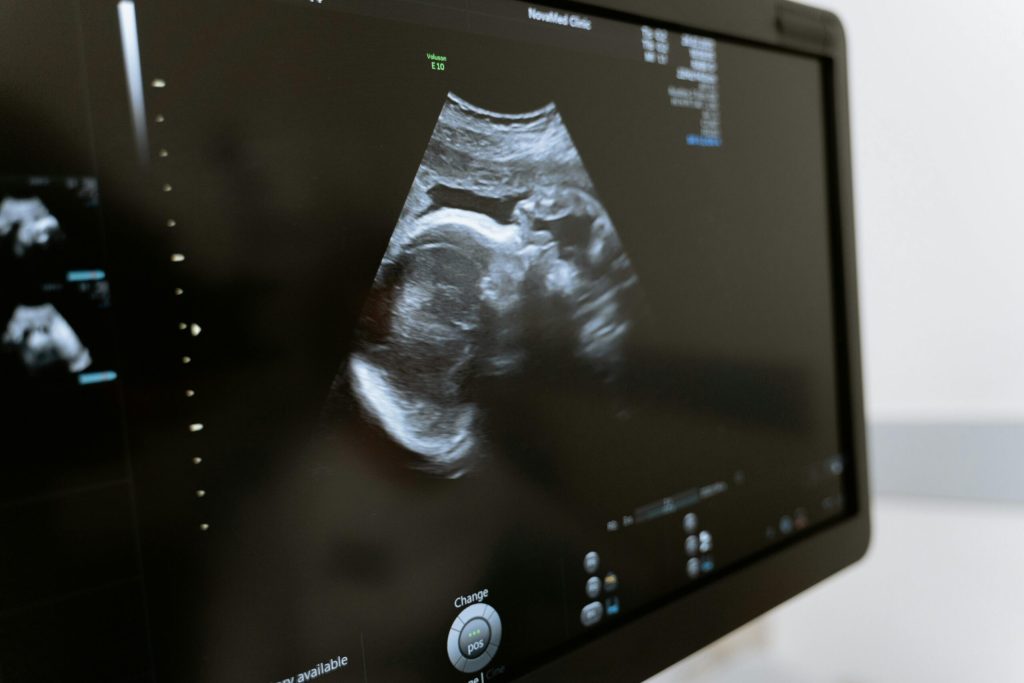

Speaking at a White House press conference on Monday, President Trump claimed that the use of Tylenol during pregnancy may be associated with a “very increased risk of autism,” and stated that the U.S. Food and Drug Administration will notify doctors about this potential risk.

The agency noted that its advice is based on “a rigorous assessment of the available scientific data,” including a 2019 review of studies on the neurodevelopment of children exposed to paracetamol in utero.